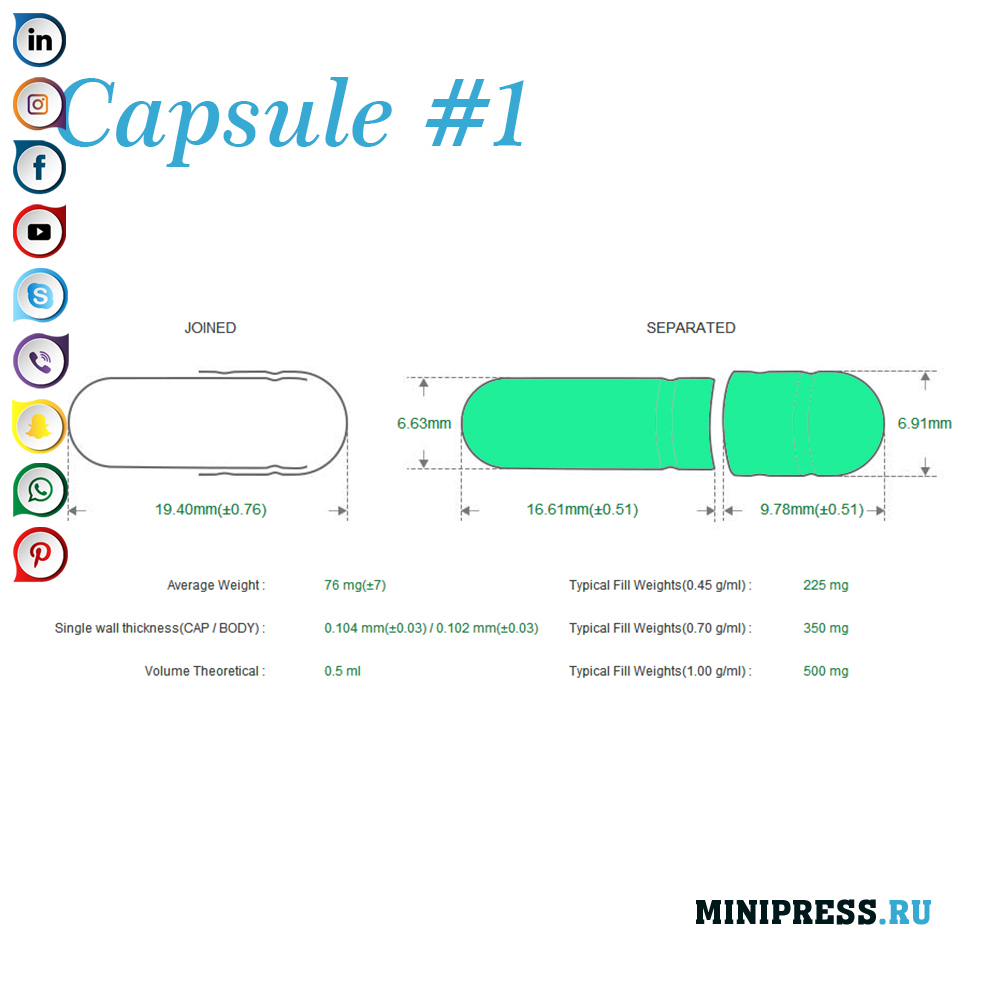

Velike zelatinskih kapsula: 000,00,0,1,2,3,4,5, A, B, C, D, E.